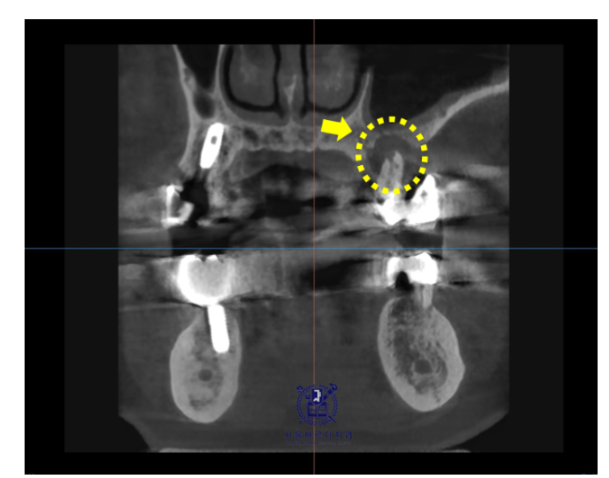

늘 분석합니다.

수술 전 불안해하시는 분들이 많은데요,

강동구 임플란트를 위해 의료진은 늘 준비합니다.

시뮬레이션을 하고

문제가 생겼을 때 대응책도 준비되어있어요.